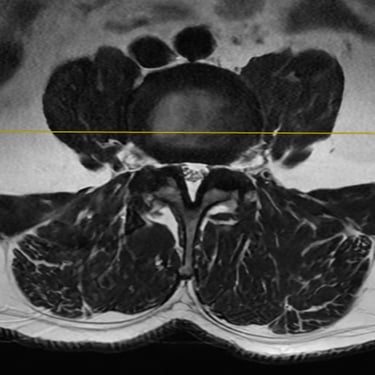

La inestabilidad de la columna lumbar ocurre cuando los segmentos vertebrales pierden su alineación y soporte normal, generando dolor lumbar crónico, limitación funcional y, en algunos casos, compresión de las raíces nerviosas. Cuando el tratamiento conservador no resulta efectivo, la fijación transpedicular (FTP) asociada a la fusión intersomática transforaminal (TLIF) representa una alternativa quirúrgica eficaz. Este procedimiento permite estabilizar el segmento afectado, descomprimir las estructuras nerviosas y restaurar la biomecánica de la columna. La combinación de fijación y fusión reduce el dolor, mejora la estabilidad vertebral y favorece una recuperación funcional segura y progresiva.